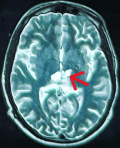

Diagnostic assessment: magnetic resonance imaging of the brain demonstrated an infiltrative thalamo-peduncular lesion with hyperintensity on T2/FLAIR sequences and faint enhancement on post-contrast T1, raising concern for an infiltrative high-grade glioma and creating diagnostic uncertainty (Figure 1, Figure 2). A stereotactic biopsy was subsequently performed. Initial histological evaluation suggested a high-grade glioma; however, immunohistochemical staining revealed strong positivity for CD117, PLAP, and OCT4, findings consistent with a pure germinoma (Figure 3, Figure 4). Staging with thoraco-abdominopelvic CT identified nonspecific pulmonary micronodules (Figure 5), while serum tumor markers remained within normal limits (Table 1). As shown above, the patient's LDH level is elevated compared to the reference range, while both β-HCG and α-FP are within normal limits. These values are important for the diagnostic evaluation and ongoing management of intracranial germ cell tumors.

Figure 2: axial T2-weighted brain magnetic resonance image showing a thalamo-peduncular mass: axial T2-weighted magnetic resonance image demonstrating a hyperintense lesion in the thalamo-peduncular region with surrounding edema and compression of the third ventricle